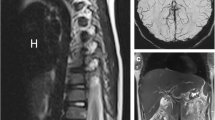

Representative GE-MRV and FE-MRV images are provided in Figs. 1, 2, 3, 4, 5, 6, 7, 8 and 9. Figures 1 and 2 show comparable quality in both GE-MRV and FE-MRV in two patients with extensive, systemic venous occlusive disease. Figures 3 and 4 compare GE-MRV and FE-MRV in two patients with portal hypertension and splenomegaly, again showing similar quality in both patients.

A 10-year-old girl with portal hypertension and splenomegaly. a, b Coronal ferumoxytol-enhanced magnetic resonance venography was performed at 3.0 T. The patient has gross splenomegaly shown on thin maximum intensity projection (MIP) (a) and a large spontaneous splenorenal shunt (arrows) shown on thick MIP (b). Note the uniform and high intravascular signal at 12 min post contrast injection

A 3-day-old girl with Shone syndrome. a, b Coronal contrast-enhanced magnetic resonance (MR) angiography was performed with gadofosveset at 3.0 T to evaluate vascular anatomy. The arterial phase (a) and venous phase (b) show good vascular enhancement. Note the left superior vena cava (arrow in b). c–e The same patient was imaged with coronal ferumoxytol-enhanced MR angiography at 3.0 T 2 years after surgery that included a Norwood procedure and bilateral Glenn shunts. The neo-aorta (arrow in c) and left Glenn shunt (arrow in e) are seen. Note the stable intravascular signal from first pass through 5 min post contrast

Figures 5 and 6 compare two neonatal patients, 2 and 3 days old, respectively. These figures show a noticeable decrease in the intravascular signal with gadofosveset by 2 min, whereas the intravascular signal with ferumoxytol is unchanged after 45 min.

Figure 7 illustrates how coexisting congenital venous anomalies, surgical shunts and veno-occlusive disease can all be assessed on FE-MRV, in this case up to 39 min following ferumoxytol infusion.

Figure 8 shows a 4-year-old dialysis-dependent patient who required venous mapping for catheter access. Repeated cannulation resulted in extensive venous occlusion in the pelvis, chest, neck and bilateral upper extremities. Diseased segments and venous collaterals are clearly visible and uninvolved systemic and portal venous structures in the abdomen and liver are visualized in detail.